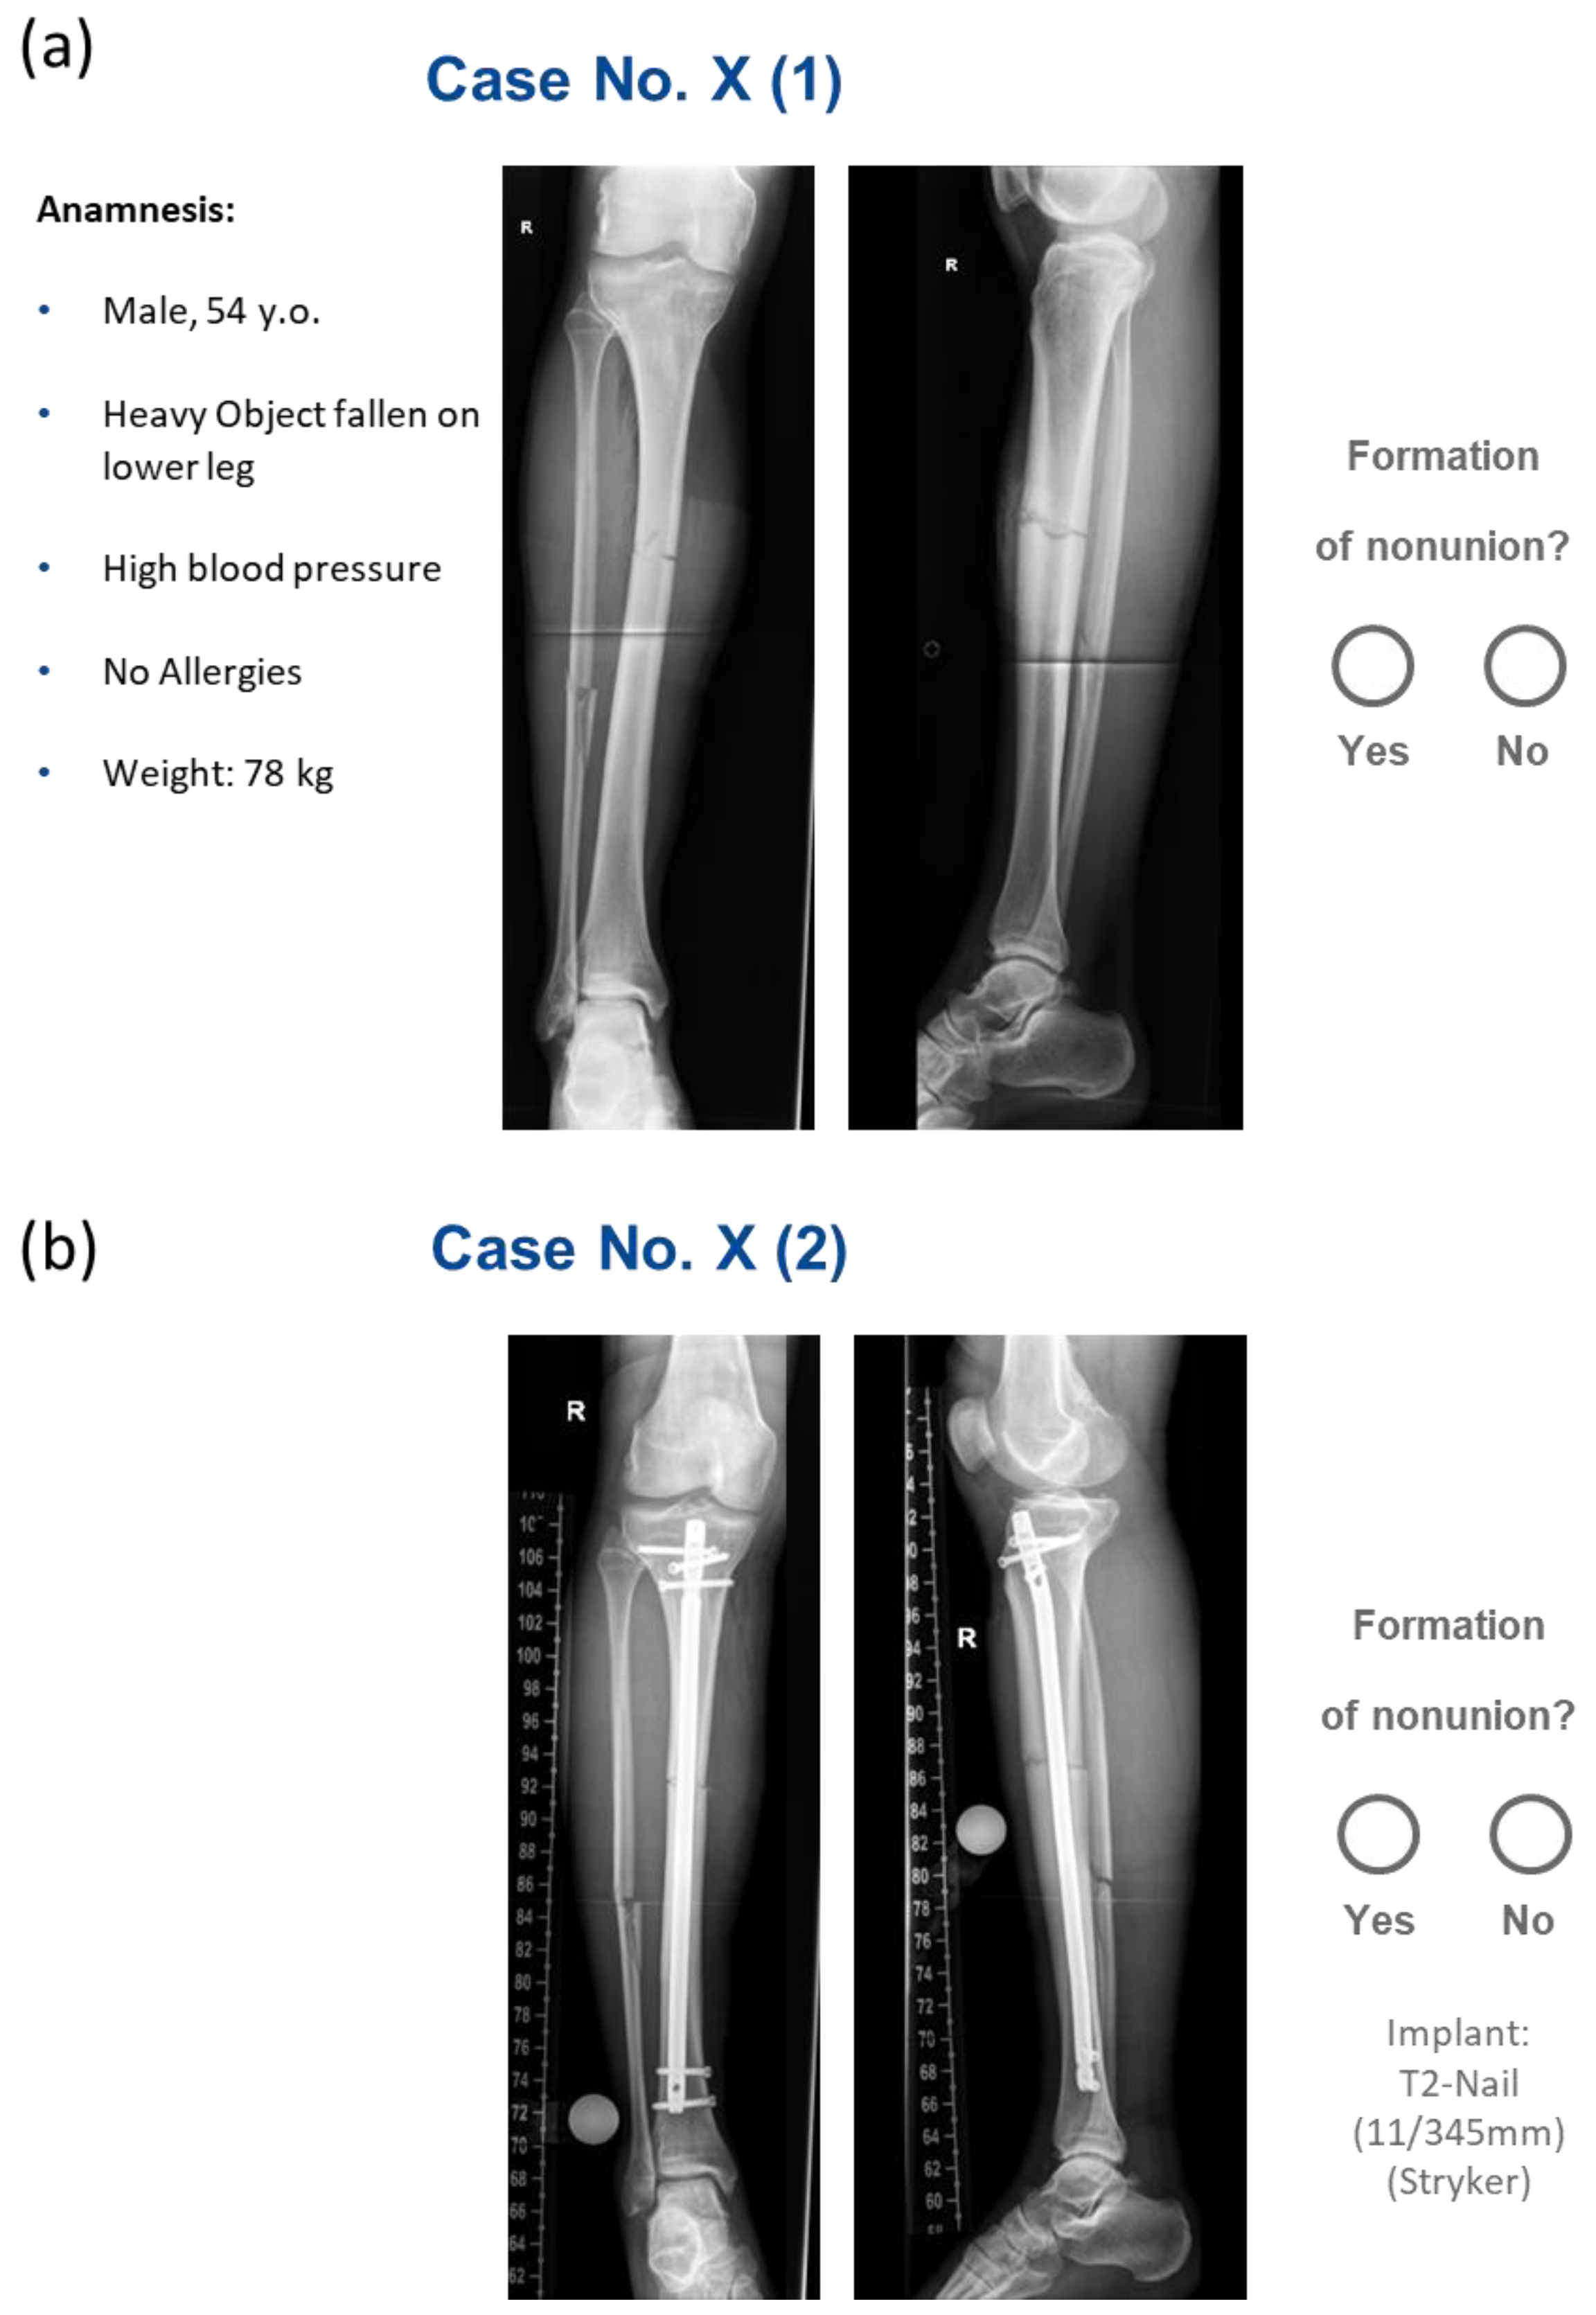

We enrolled 98 patients, 20 of whom were diagnosed with NU, while 78 subjects showed normal fracture healing. Figure 1 illustrates a representative case.

Figure 1. Demonstration of a patient case as presented to the clinical raters for healing prediction: (a) preoperative biplanar X-rays and patient background information; (b) postoperative biplanar X-rays (original text in German). R = right side.